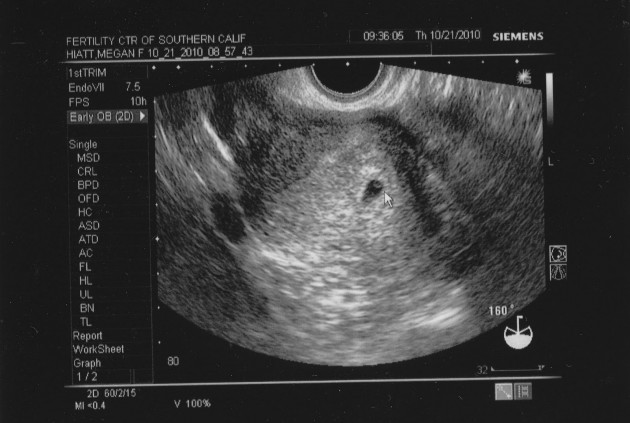

Некоторым девушкам хочется знать о возможности беременности раньше, чем ждать пока возможно будет сделать УЗИ. Ведь такой способ может подтвердить беременность только на третьей или четвертой неделе после зачатия. Согласитесь, что это длительное время и спокойно ожидать его не получится у многих женщин.

УЗИ – верный способ определить беременность, но после третьей-четвертой недели

Когда женщина узнает о задержке месячных, она начинает делать тесты на беременность. И при положительном результате начинает задумываться о том, кто же там. Девочка или мальчик? Такой вопрос может решить УЗИ. На ультразвуковом исследовании можно увидеть какая именно беременность, сколько плодов, нет ли отклонений. На УЗИ врач может заметить признаки замершей беременности на очень ранних сроках. Такой диагноз можно поставить лишь при данном обследовании и никак больше.

Наиболее достоверные способы выявления беременности — анализ крови на ХЧГ и ультразвуковое исследование. По анализу крови можно определить беременность на ранних сроках и даже выявить некоторые её осложнения. Код 2.36.